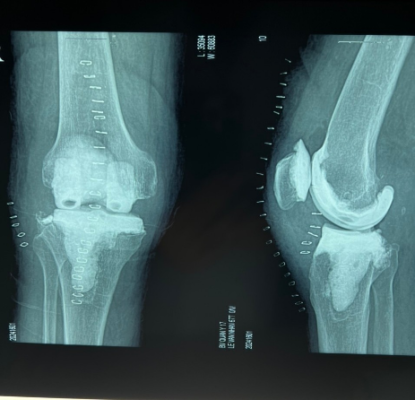

– XQuang: Có hình ảnh khớp gối nhân tạo.

Hình 2. Xquang khớp gối thường quy

Hình 5. Xquang khớp gối, phục hồi chức năng sau mổ